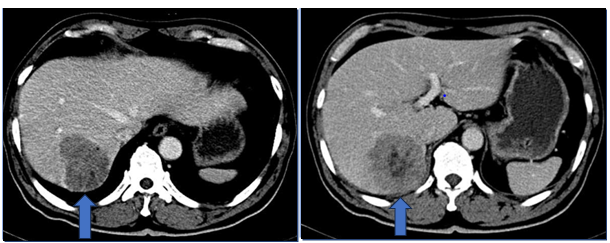

Hình ảnh cắt lớp vi tính ổ bụng sau 3 tháng:

Hình 3: Bên trái: trước điều trị u gan hạ phân thùy V kích thước 48x51mm. Bên phải: sau điều trị 3 tháng u gan giảm kích thước 22x25mm